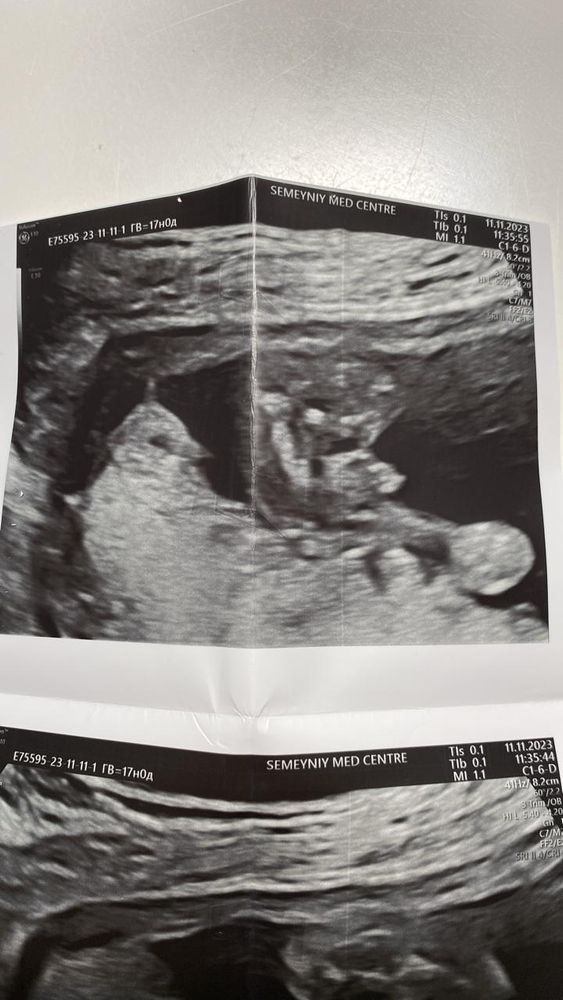

у нас было гендер - пати, и только после него открыли фото узи, у нас мальчик , но сколько бы я не разглядывала фото , не могу понять где увидели то самое мужское достоинство 🤭

Опытные, помогите понять🙏🏼